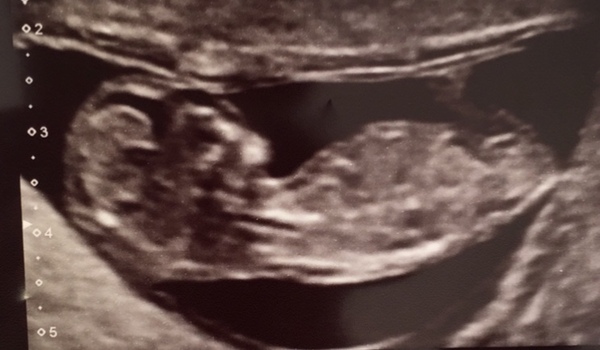

@dontquit great picture! They look like they are waving hello!!

@dontquit great pic!

Congratulations to the ladies with the beautiful scan pics! And good luck to those with scans today. Can't believe we're into the 12-week scans already.